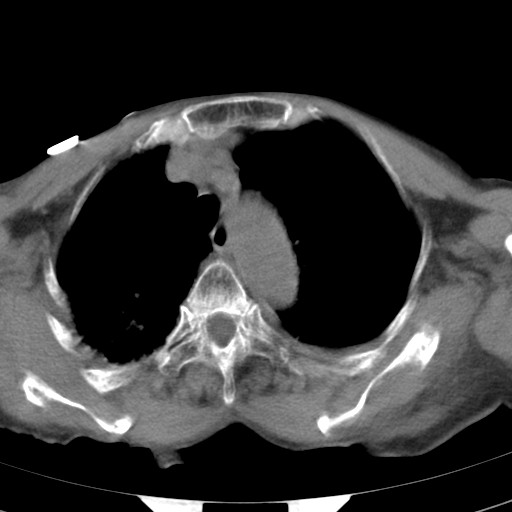

女,93岁,摔伤后检查。

右肩甲骨粉碎性骨折,上传骨窗

右侧锁骨\\肩胛骨骨折、右侧湿肺,心功能不全伴双侧胸腔积液,右下肺膨胀不全,左膈破裂或食管裂孔疝,冠脉钙化,心包少量积液,请上传骨窗.

右肺炎症,心功能不全伴双侧胸腔积液,右下肺膨胀不全,食管裂孔疝,冠脉钙化,心包少量积液,左侧肋骨骨折,右肩甲骨粉碎性骨折。93岁,高寿哇!

右肺炎症,心功能不全伴双侧胸腔积液,右下肺膨胀不全,食管裂孔疝,冠脉钙化,心包少量积液,左侧肋骨骨折,右肩甲骨粉碎性骨折。